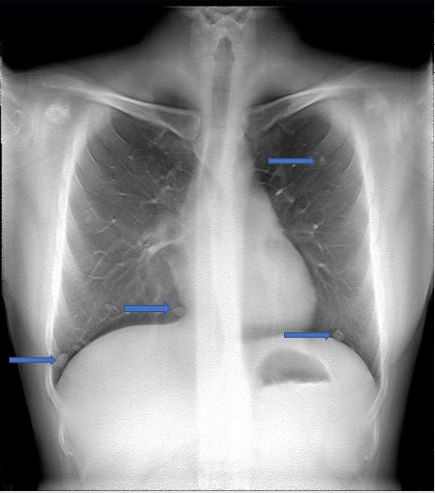

容积图像:

影像描述: X线平片:左肺内上叶、下叶见结节样密度增高影 容积图像:双肺见多个大小不等结节样密度增高影 影像诊断:肝癌肺内转移 病例点评: 容积断层图像显示双肺多发结节,较常规X平片所见病灶明显增多。相对于传统胸部X线平片,断层容积图像可以检出更多的肺转移病灶,为治疗方案的制定提供更多的影像学信息。